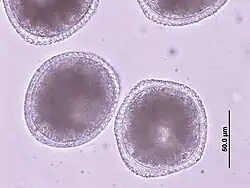

T. canis is an 8 to 18 cm long nematode that parasitizes (lives as a parasite) in the small intestine. There, the adult females release approximately 85 μm large unfurrowed eggs, whose shell is thick and rough (golf ball-like) and which are released into the outside world via the feces. The period from infection to egg laying (prepatency) is three to six weeks, depending on the route of infection and the age of the dog. T. canis does not require an intermediate host for development, but infection of dogs can occur via collective hosts such as rodents and birds. In collective hosts (paratenic hosts), no complete development cycle of the parasites occurs, but infective stages can accumulate in them through multiple infections. In principle, three routes of infection are possible for T. canis: peroral infection and transplacental and galactogenic infection, which are much more common in puppies.

T. leonina is 6 to 10 cm long, the eggs are about 80 μm in size and thick-shelled. Unlike the eggs of T. canis, they have a smooth surface. Infection occurs perorally by ingestion of eggs from contaminated (polluted) food or via collective hosts such as rodents, birds, reptiles, or arthropods. The prepatency is 7 to 10 weeks.[2]

In the case of worms in vomit, the diagnosis can already be made without special examinations. A roundworm infection can be detected with relative certainty by microscopic detection of the eggs extracted from the feces by the flotation method, but only after the expiration of the prepatency period.[2]